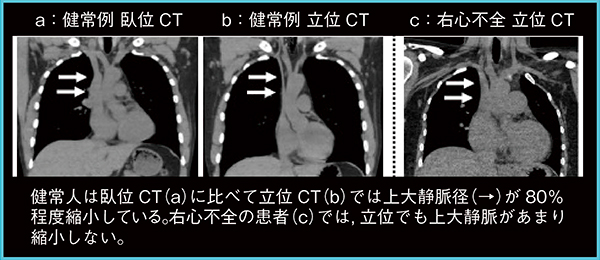

静脈は体位によって径が変化することが知られているが,これまでに全身を系統的に評価されたことはなかった。健常例における臥位と立位のCT画像(図5 a,b)を比較したわれわれの検討では,立位では上大静脈径(→)が約80%縮小し,逆に下大静脈径は約37%増大した。また,横隔膜の高さでは,臥位と立位で静脈径は変わらず,変化率は部位によって異なることが明らかとなった1)。一方,心不全の患者では,立位でも上大静脈径があまり縮小しないため(図5 c→),静脈径の変化率は心不全の重症度と相関すると考えられた。

そこで,臥位および立位のCTで計測した上大静脈断面積と心臓カテーテル検査における右房圧との関係を検討したところ,AUC(Area Under the Curve)は立位CTで0.91,臥位CTでは0.78と,立位CTの方が良好に相関していた。立位CTにて右房圧をある程度推測することで,心臓カテーテル検査の一部を置換できれば,侵襲的検査の削減に貢献すると考える。

図5 心不全の重症度判定への応用